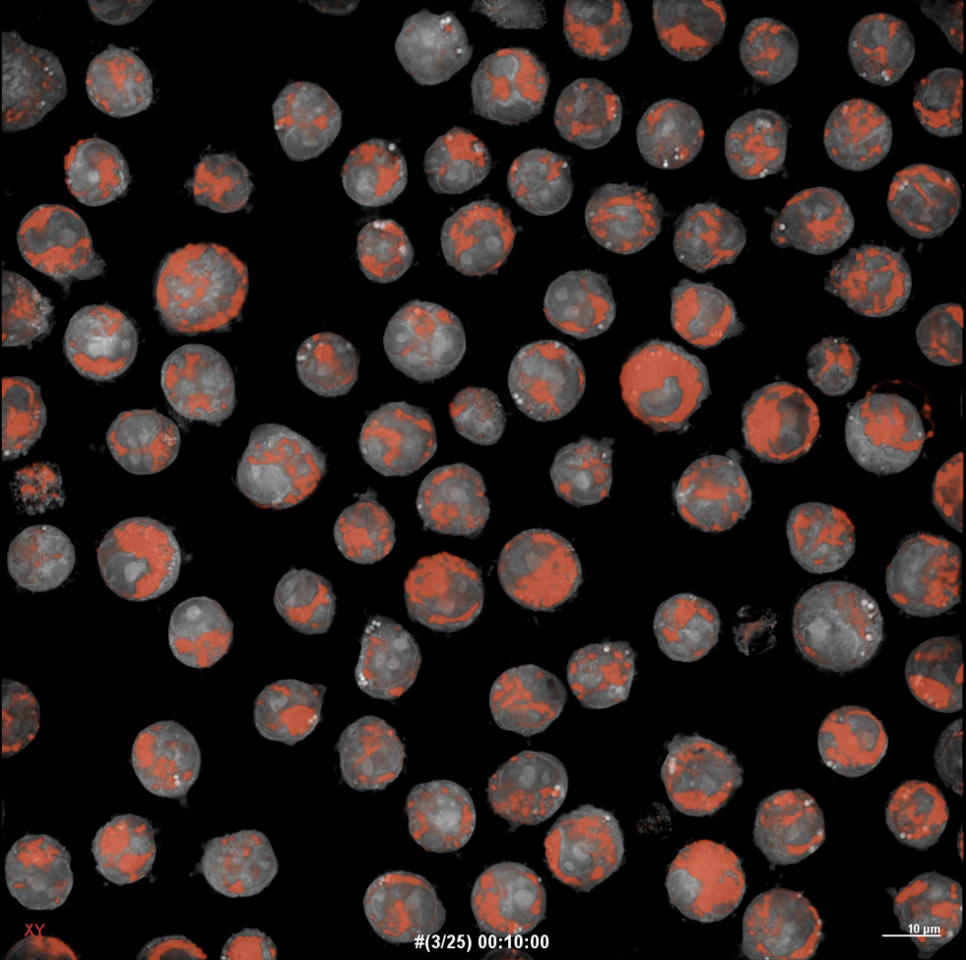

We previously examined TMQ0153 for its potential anti-cancer effects on chronic myeloid leukemia (CML) cells 4. Prior findings indicated that TMQ0153 disrupts mitochondrial function and increases oxidative stress by elevating ROS levels and promoting the accumulation of cytoplasmic Ca²⁺. Additionally, we observed decreased intracellular glutathione (GSH) levels during the early stages of TMQ0153-induced autophagy and necroptosis in CML cells. The change in oxidative stress levels caused by TMQ0153 affects mitochondrial homeostasis, leading to various forms of cell death, including immunogenic cell death (ICD), a chemotherapy-induced tumor cell death. These findings suggest that TMQ0153 is a promising agent for targeting mitochondria. Next, we investigated TMQ0153, focusing on mitochondrial metabolism and dynamics in AML.

TMQ0153 exerts its anti-leukemic activity by selectively targeting the mitochondrial fusion protein OPA1, which is often upregulated in AML cells with adverse risk profiles. Inhibiting OPA1 leads to disrupted mitochondrial dynamics, loss of cristae integrity, and mitochondrial membrane depolarization. These structural disruptions are accompanied by a metabolic shift from oxidative phosphorylation (OXPHOS) to glycolysis, elevated ROS levels, and marked apoptotic cell death.

A mechanistic overview describing the effect of TMQ0153.